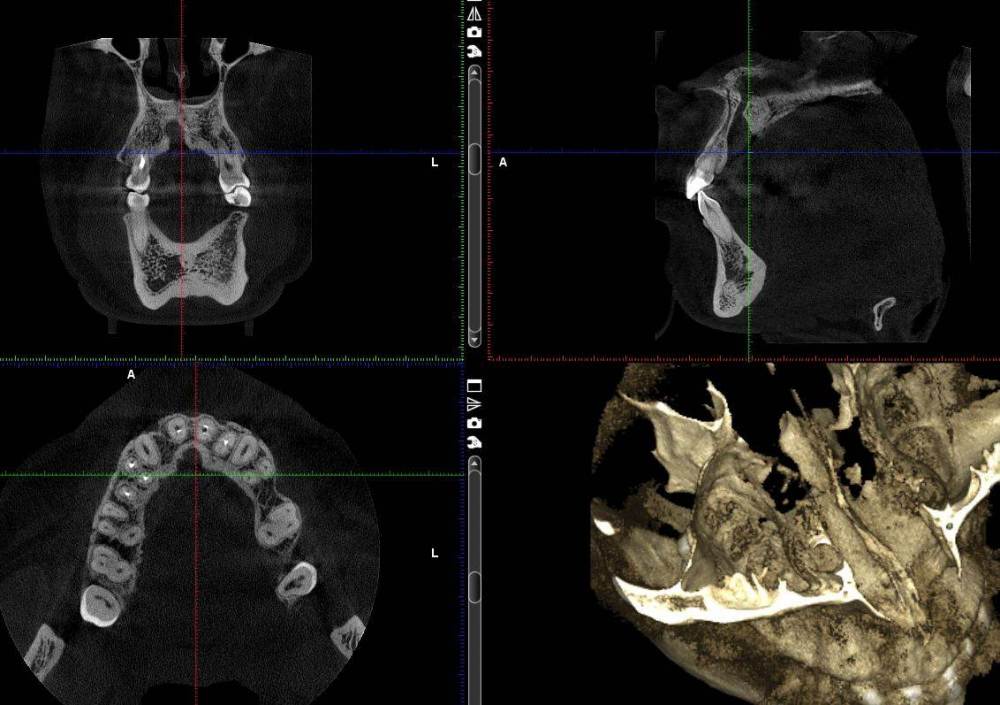

tati_dom Опубликовано 12 мая, 2021 Поделиться Опубликовано 12 мая, 2021 (изменено) Добрый день! Подскажите что это вообще такое, что с этим делать. Прием у врача только завтра. М. 26 лет, в 10 лет был удален лишний по количеству зуб, который рос вторым рядом. Как сказал тогда врач зуб был достаточно большим. Сейчас после небольшой простуды, сильно заболел толи зуб толи десна, с температурой до 38, плохим самочувствием. Сначала перелечили передние зубы, к вечеру стало хуже, вернулись в клинику, назначили антибиотики послали на КТ. После антибиотиков стало легче. На КТ такая картина. Зуб был удален на месте этой "дырки", не срослась кость за эти годы? Изменено 12 мая, 2021 пользователем tati_dom Ссылка на комментарий

сирена Опубликовано 12 мая, 2021 Поделиться Опубликовано 12 мая, 2021 Это называется "Киста резцового канала",она удаляется хирургически. Ссылка на комментарий